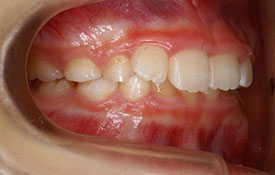

| プロフィール | 42歳 女性 |

| 所見 | 他院で行われた矯正歯科治療後の後戻りに悩まれて来院されました。 アイライナーの装着は、1日平均20時間ほどでした。 |